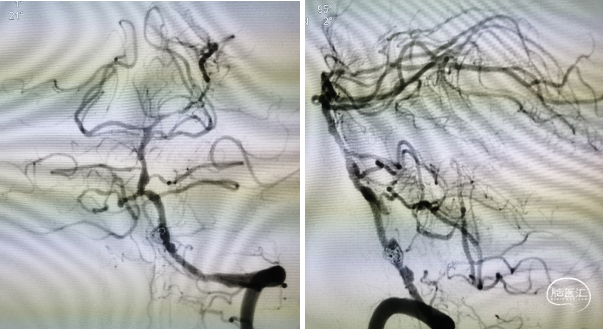

首先尝试并行式支架释放,但ProwlerPlus通过后SL-10无法进入动脉瘤内,考虑动脉瘤近端狭窄较重,考虑患者血管情况较差,未尝试强行通过,遂考虑穿支架网眼。尽管选择的是4.5 mm×37 mm的EP支架,但长度仍然捉襟见肘,头端尝试释放于基底动脉时末端距离不足,考虑椎基底交界处血管扩张情况尚满意,遂将支架释放于椎动脉

穿支架网眼动脉瘤近全栓塞(Target 360 Ultra 3 mm×6 cm、Target 360 Ultra 2 mm×6 cm

Gateway 2.0 mm×15 mm球囊命名压缓慢后扩支架